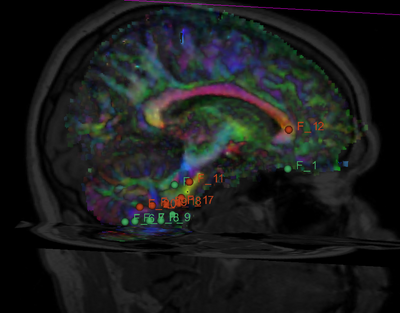

Develop a quick (< 10 min.) affine-based registration between multi-modality images for use in the AMIGO surgery suite. This module supports a fast registration using a small number of fiducials (3-5) and results in an accurately registered moving image. During this project week, we will refine the GUI and if necessary, complete work on the fiducial registration module in Slicer4.

Unregistered.png Fiducials-pre-registered.png FiducialsRegistrationResult.png